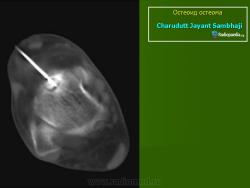

При рентгенологическом исследовании остеоид-остеома обнаруживается как субкортикально расположенный участок окостенения, окруженный ободком остеосклероза, ширина которого увеличивается по мере прогрессирования опухоли. При этом центральная часть опухоли становится менее заметно. Граница между центральной светлой зоной и склеротическим ободком, отчетливая в ранний период, со временем стирается вследствие того, что центральная зона опухоли подвергается оссификации и обызвествлению, которые распространяются центробежно. Рост кортикальных и субпериостальных остеоид-остеом сопровождается также реактивным склерозом- Имеются указания и на то, что если новообразование растет в костномозговом канале, то в соответствующей кости развивается остеопороз. Обычно опухоль легко вылущивается из окружающей кости и макроскопически представляет собой мелкозернистую, красновато-бурую костную ткань. Остеоидную остеому, как правило, удаляют хирургическим путем. Рецидив возможен, но практически не встречаются. Если он и происходит, то спустя 10 лет и позднее после удаления первичного узла опухоли.

Рентгенологическая картина. На обзорных рентгенограммах очаг поражения характеризуется утолщением и уплотнением кортикального слоя кости вокруг небольшого литического гнезда.

Osteoid Osteoma: Subperisosteal, capitatum